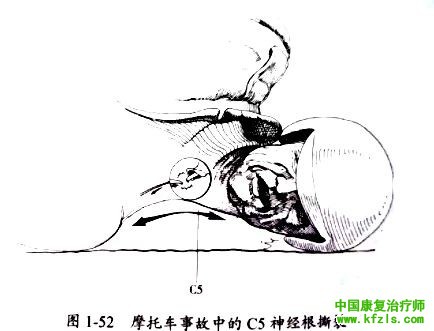

在摩托车交通事故中,颈神经根经常会从脊髓上撕裂。当驾驶员从摩托车上摔下时,头部和颈部侧方着地与地面撞击后肩部压低,导致神经根拉伸,严重时导致撕裂,C5 和C6神经根损伤最为常见(图1-52)。

体格检査即可明确结果: C5神经根功能丧失,C5支配区域会出现运动障碍及感觉缺失,如三角肌瘫痪,上臂上外侧角触觉障碍或麻痹,肱二头肌反射(C5~C6)减退或消失,脊髓造影可示撕裂点一C5神经根的起源点(C4和C5椎体之间)。这种永久性损伤无法手术修复,通常无恢复可能。